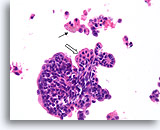

Ductaal carcinoom

Ductaal carcinoom, Borst FNA, ThinPrep®.

Een cellulaire, discohesieve, monotone ductale celpopulatie met stratificatie van de kernen is aanwezig.

10X

Ductaal carcinoom, Borst FNA, ThinPrep®.

Een cellulaire, discohesieve, monotone ductale celpopulatie met stratificatie van de kernen is aanwezig.

10X

Ductaal carcinoom, Borst FNA, ThinPrep®.

Bij een sterkere vergroting kunnen gerandomiseerde polariteit en mild nucleair pleomorfisme duidelijk worden waargenomen.

40X

Ductaal carcinoom, Borst FNA, ThinPrep®.

Bij een sterkere vergroting kunnen gerandomiseerde polariteit en mild nucleair pleomorfisme duidelijk worden waargenomen.

40X